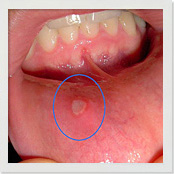

| 「アフタ性口内炎」 |

| たいていの口内炎は、「アフタ性口内炎」となります。炎症部分が白くなって、強い痛みを伴います。症状は口内の粘膜に限らず、舌やその下の口底などにも見られます。再発の可能性が高く、しつこい口内炎といえます。 |